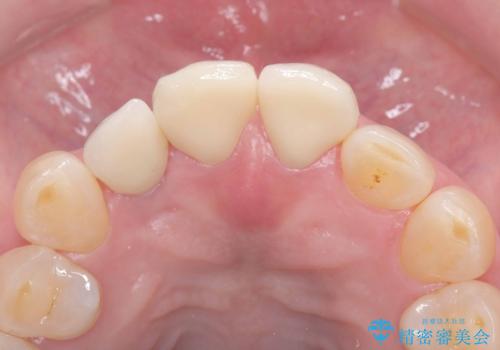

前歯の隙間とへこみが舌で触ると気になる|矯正治療は絶対にしたくない|抜歯即時インプラント+オールセラミッククラウンで審美修復

- 前歯の隙間とへこみが気になり、特に舌で触ると気になってストレスを感じるとのことで来院された患者様です。

そのため今回は、右上2番を抜歯し、右上1番および左上1番をオールセラミッククラウンで審美的に修復しました。